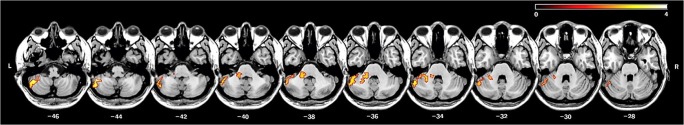

The affective component of CCAS has been associated with damage in the posterior vermis and the fastigial nucleus [12, 58–60]. In the initial report of CCAS [12], the changes in affect in individuals with acquired CB lesions tended to resolve with time, suggesting that the affective changes may be due to remote disturbance in other regions. However, individuals with abnormal midline CB development show persistent changes in affect, but also cognitive impairment, even if the pathology is restricted to the vermis [58]. To date, there has been minimal sophisticated lesion-symptom mapping in the affective domain. One exception is a recent voxel-based study by Kim and colleagues [61], where left posterior CB damage was associated with depressive mood severity in 24 patients with isolated CB stroke (Fig. 2).

Fig. 2.

CB VLSM on depressive symptom severity. Figure adapted from [61] © 2017, with permission from Elsevier